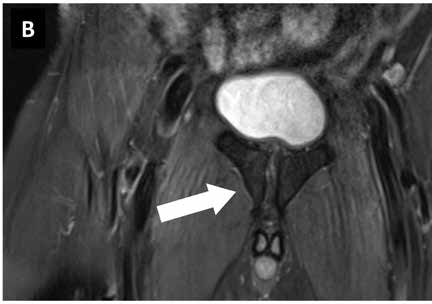

Images: MRI pubic bone branch football player 1st German Bundesliga. (A) Findings before start of therapy with focused ESWT, (B) findings 6 weeks later with no pain under stress.

Images courtesy of sportärztezeitung.